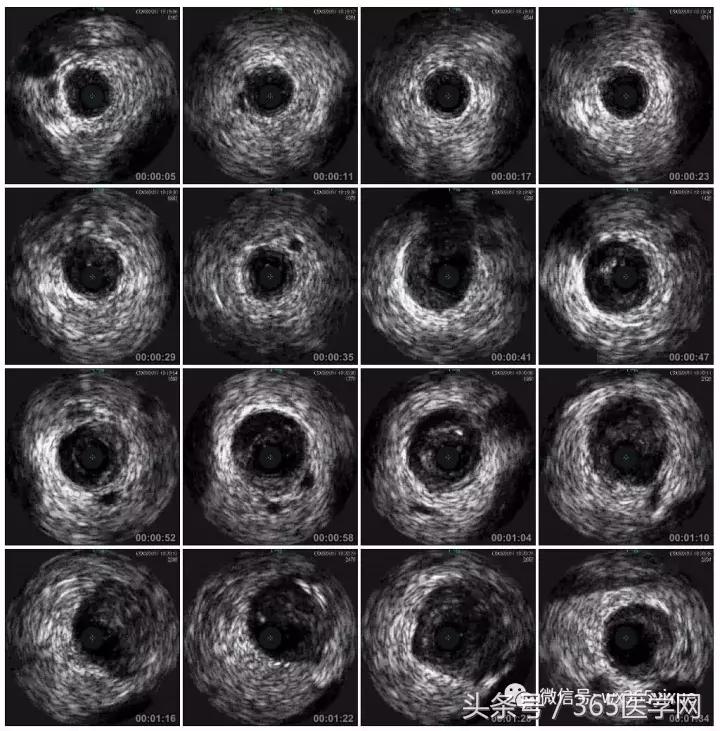

首先:IVUS指导下干预LAD

RCA闭塞段球囊扩张后IVUS

支架术后IVUS